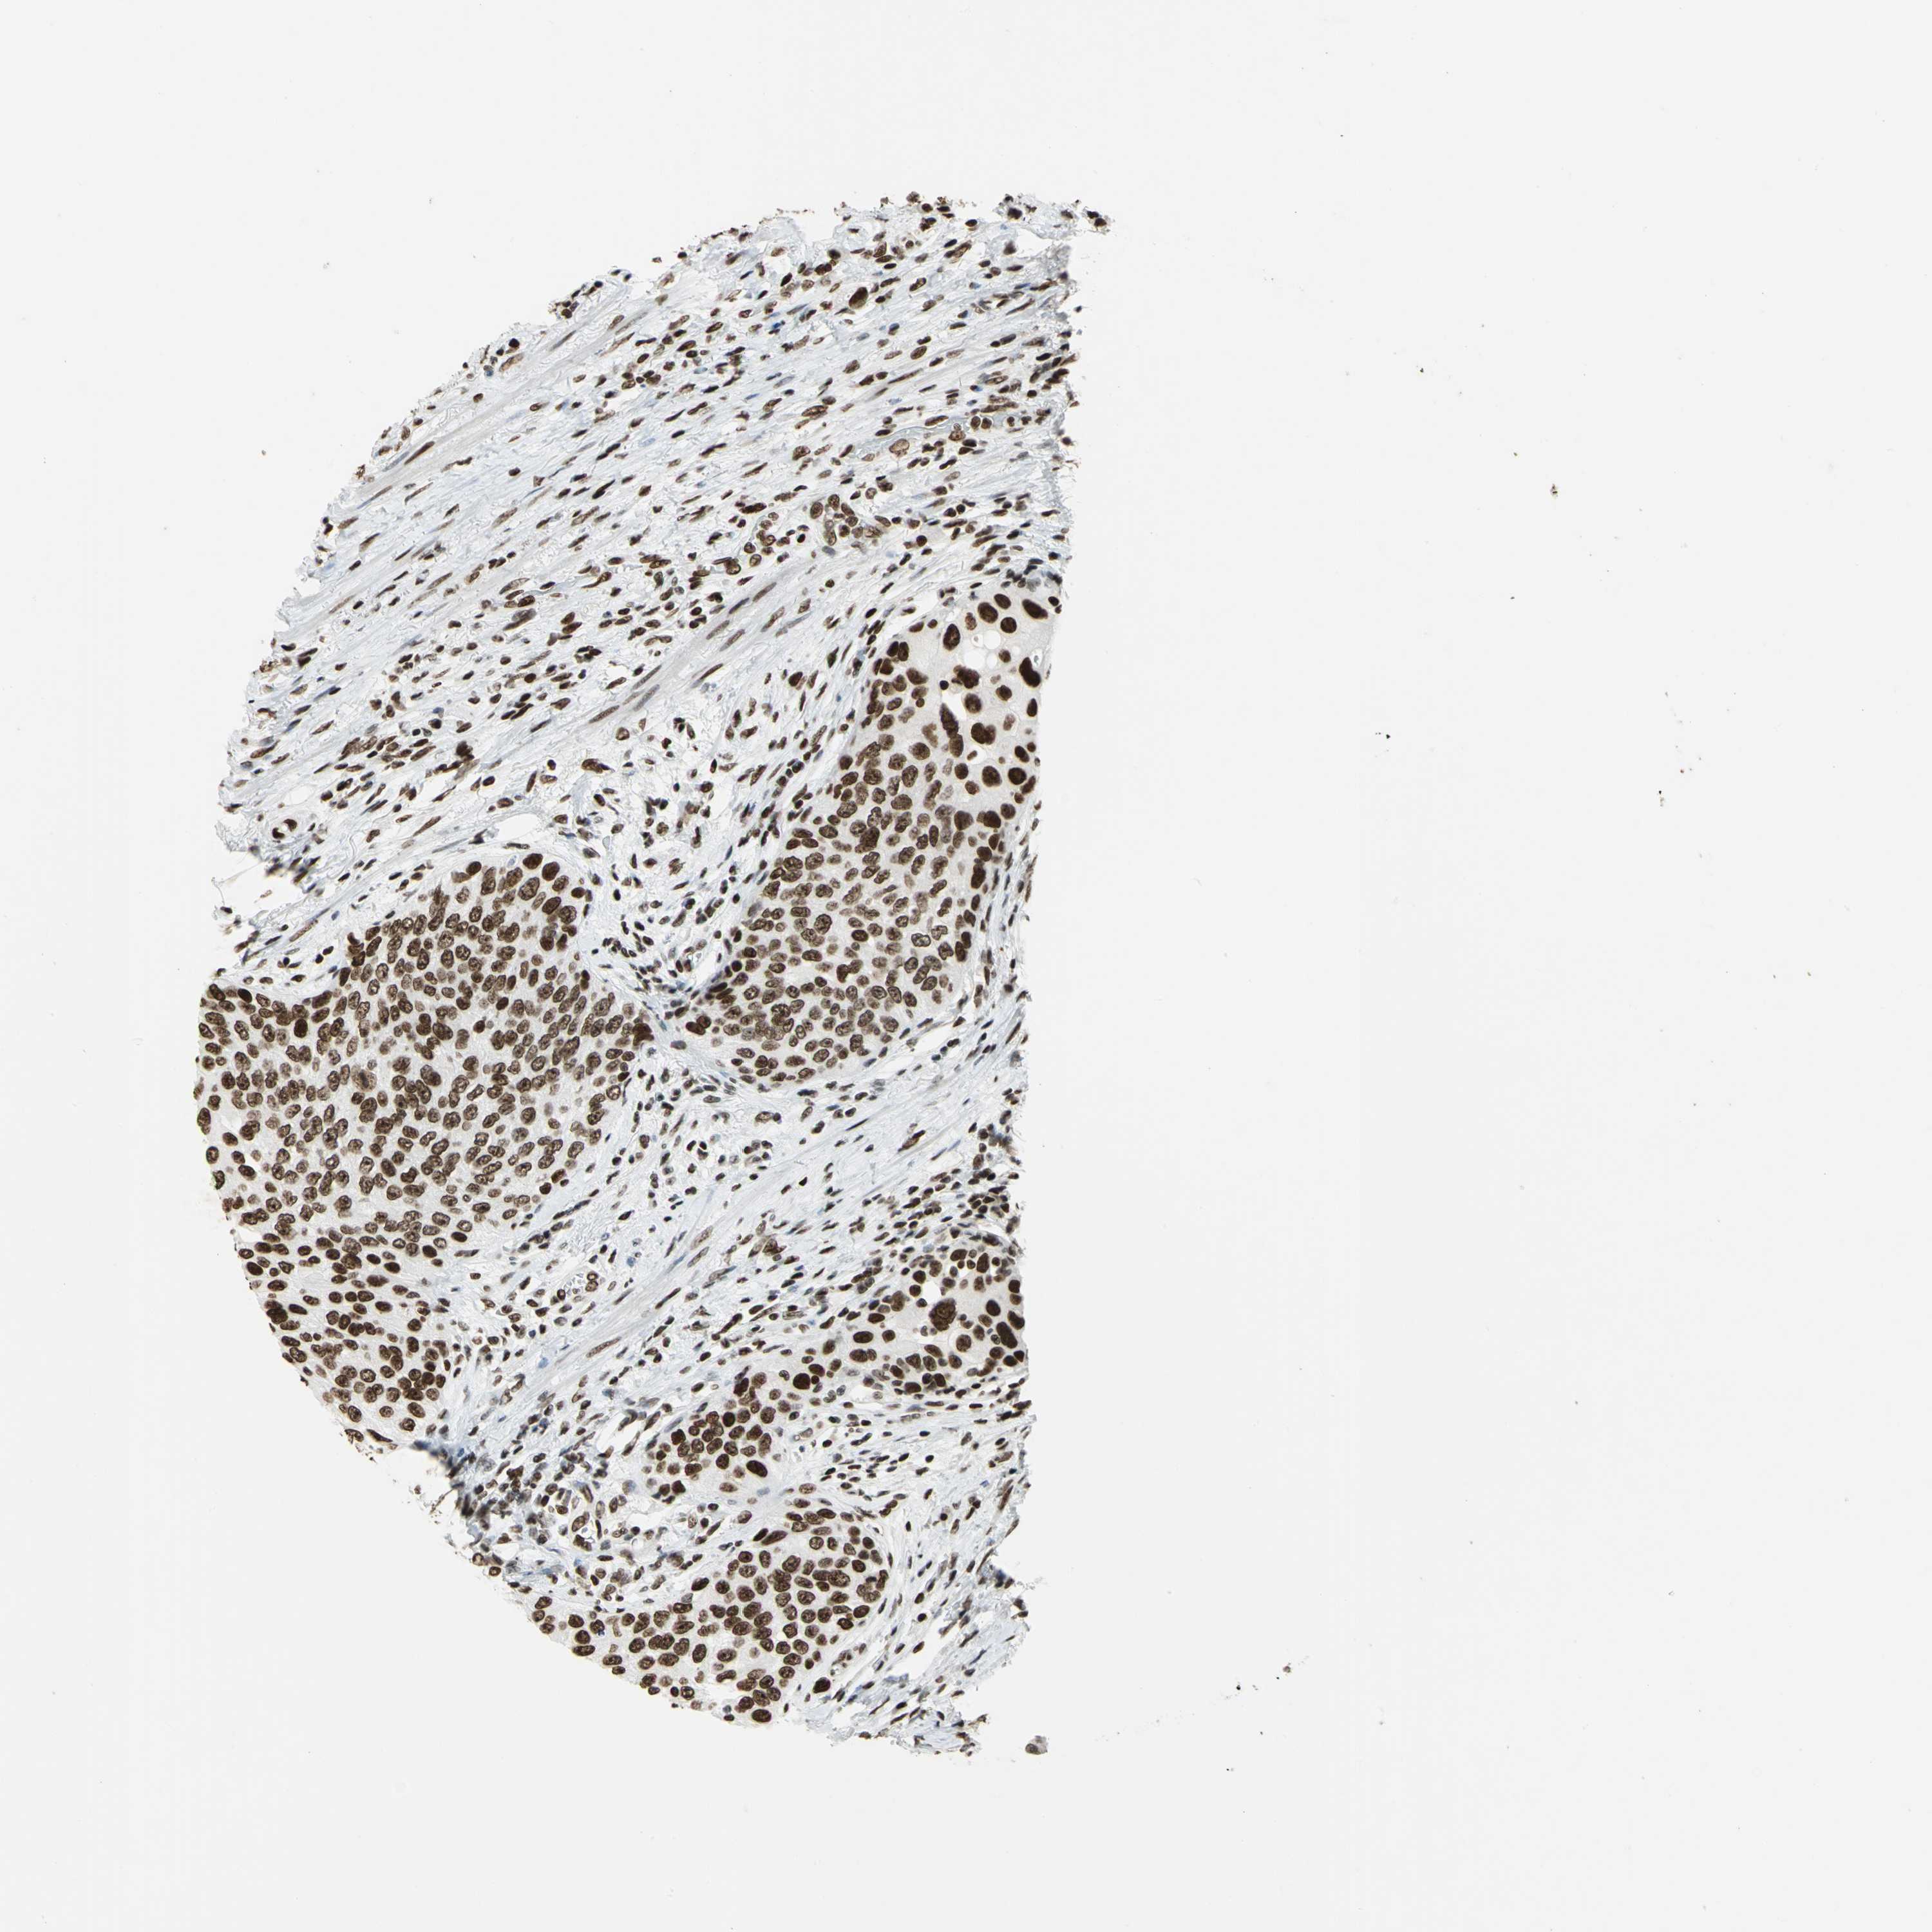

UROTHELIAL CANCER - Protein expressioni

A mouse-over function shows sample information and annotation data. Click on an image to view it in a full screen mode. Samples can be filtered based on level of antibody staining by selecting one or several of the following categories: high, medium, low and not detected. The assay and annotation is described here.

Antibody stainingi

Antibody staining in the annotated cell types in the current human tissue is reported as not detected, low, medium, or high, based on conventional immunohistochemistry profiling in selected tissues. This score is based on the combination of the staining intensity and fraction of stained cells.

Each image is clickable and will lead to virtual microscopy that enables deeper exploration of all samples and also displays staining intensity scores, fraction scores and subcellular localization as well as patient and tissue information for each sample.

Antibody HPA003506

Antibody CAB005873

Urothelial carcinoma, High grade

Urothelial carcinoma, Low grade